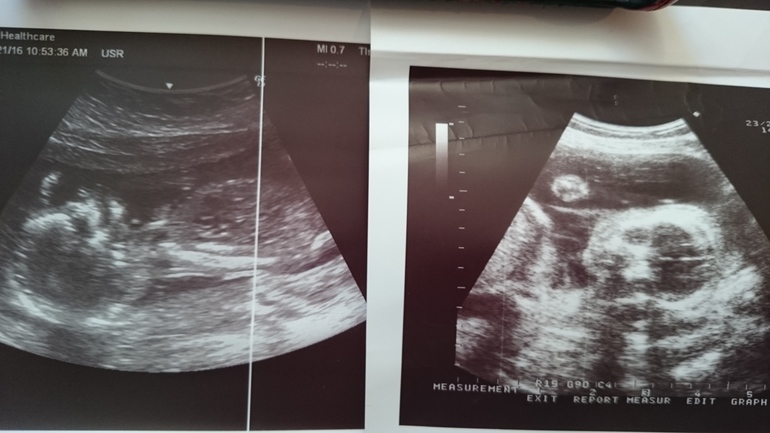

Завтра у нас экватор, 20 неделек. На прошлой неделе сделала УЗИ так как переживала что шевеления плохие, но оказалось всё отлично. Просто ляля ещё видимо маловата, но на экране прям пляски, и зевала, (на левом фото видно), и пальчик сосала. Но пол не увидели, сидит попой вниз по турецки. Эх, ну ладно, подождём второго скрининга, может поменяет положение и разглядят))) Вот как интересно получается, форма головы у деток совсем разная, у сына овальная, а у второго кругленькая, и в животе такие аккуратные пиночки. На этом сроке с первым у меня уже бугры из живота торчали в разные стороны. Может там всё таки девулечка??? Ждёмс...